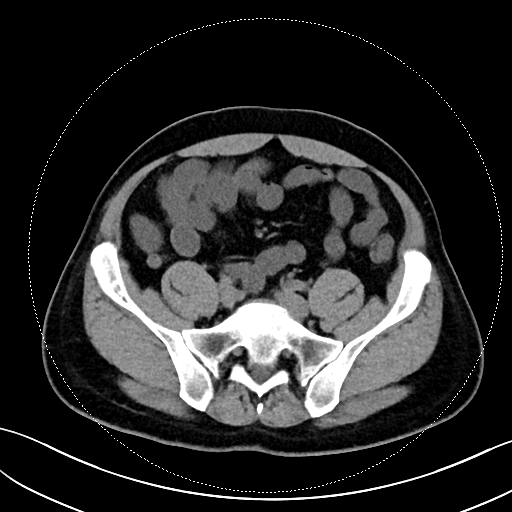

该患者的症状表现为钝痛,与进食、排便没有关联,也未出现发热、腹泻等伴随症状。在外院检查时,常规实验室检查如血常规、CRP、粪便钙卫蛋白均无异常,胃镜、结肠镜、胶囊内镜及超声内镜检查也未发现溃疡、肿瘤或克罗恩病的迹象。转诊至我院后,马师洋副教授团队另辟蹊径,对患者的腹部 CT 进行了细致入微的 「像素级」 阅片,并通过三维重建分析,敏锐地捕捉到阑尾根部呈现 「折角样」 扭曲,管腔局部狭窄且粘膜皱襞紊乱,虽无典型阑尾炎的周围脂肪条索、粪石等征象,但这一发现与患者的疼痛定位高度吻合,初步判断为非梗阻性阑尾功能障碍。